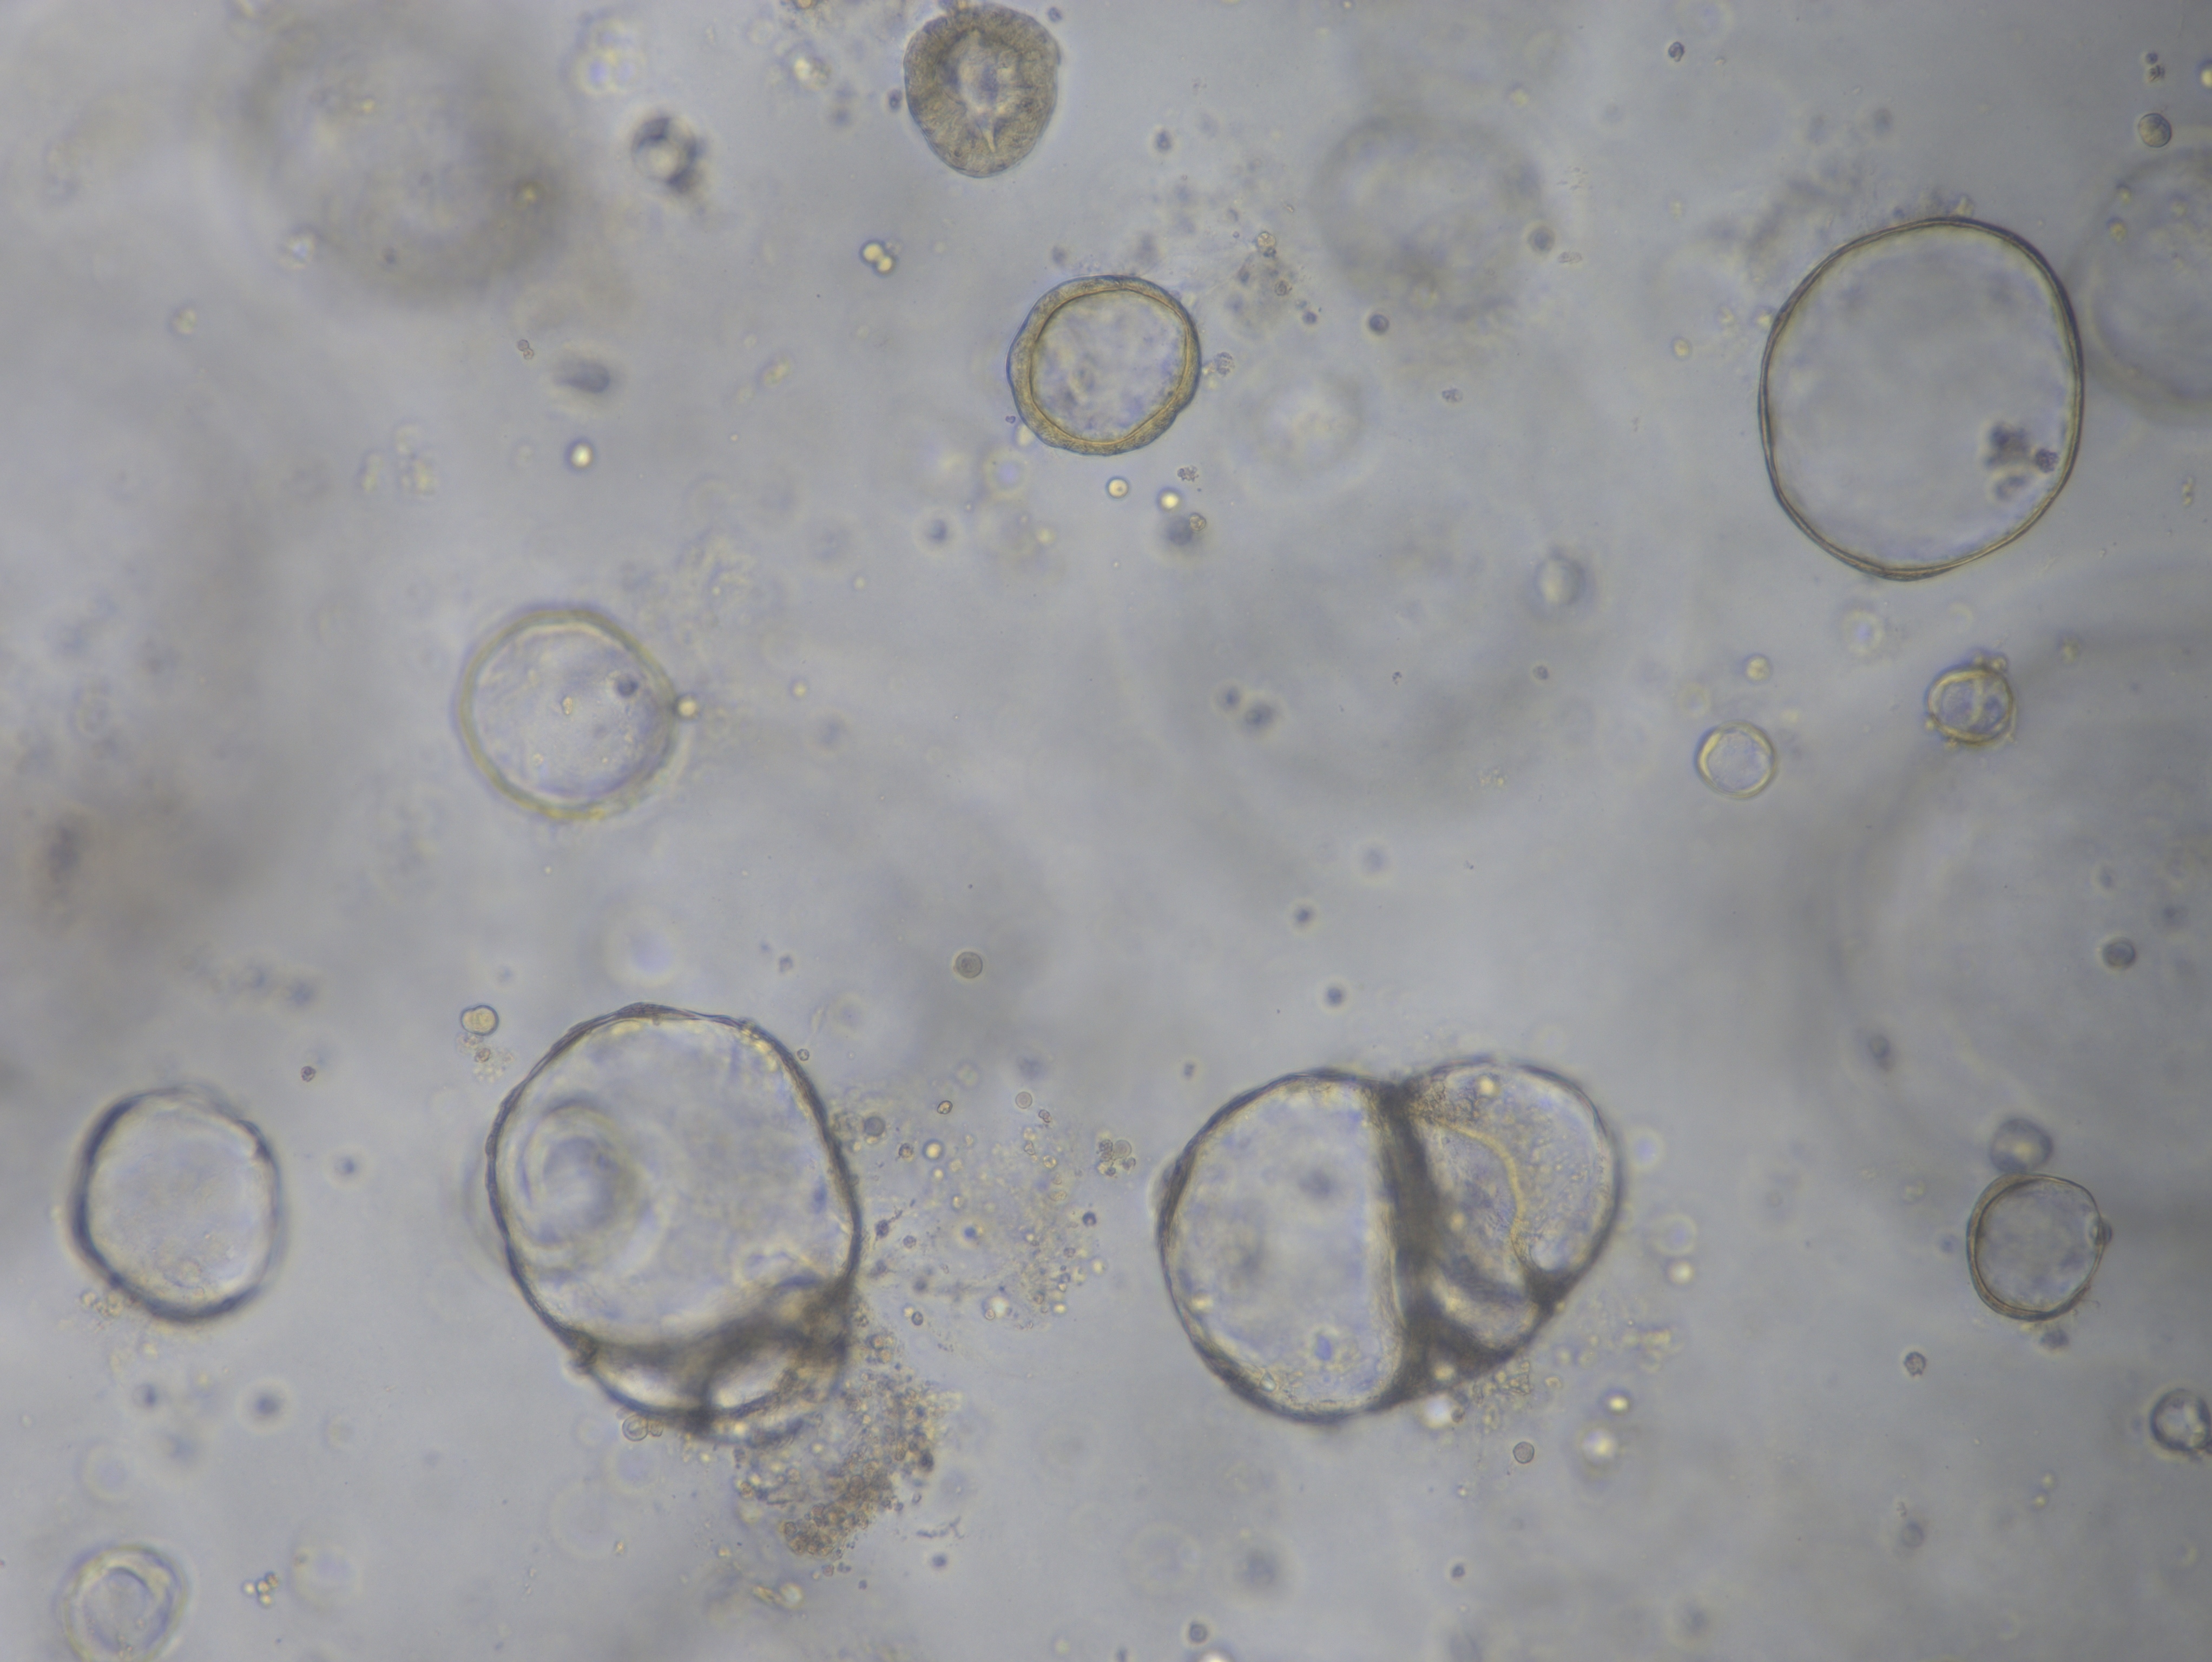

产品介绍 Kinlogix Human Ovarian Cancer Organoid Kit /Medium(人卵巢癌类器官分离培养试剂盒/培养基)是一款用于建立和维持人卵巢癌类器官的完全培养基及试剂。源自患者的癌症类器官可概括原始肿瘤的基因组和病理特征,因此对医学研究和精准医学具有很大的前景。

10. 凝固后加入500ul人卵巢癌类器官培养基到24孔板,置于细胞培养箱中进行培养,每天观察类器官生长情况,每隔1d更换培养液。